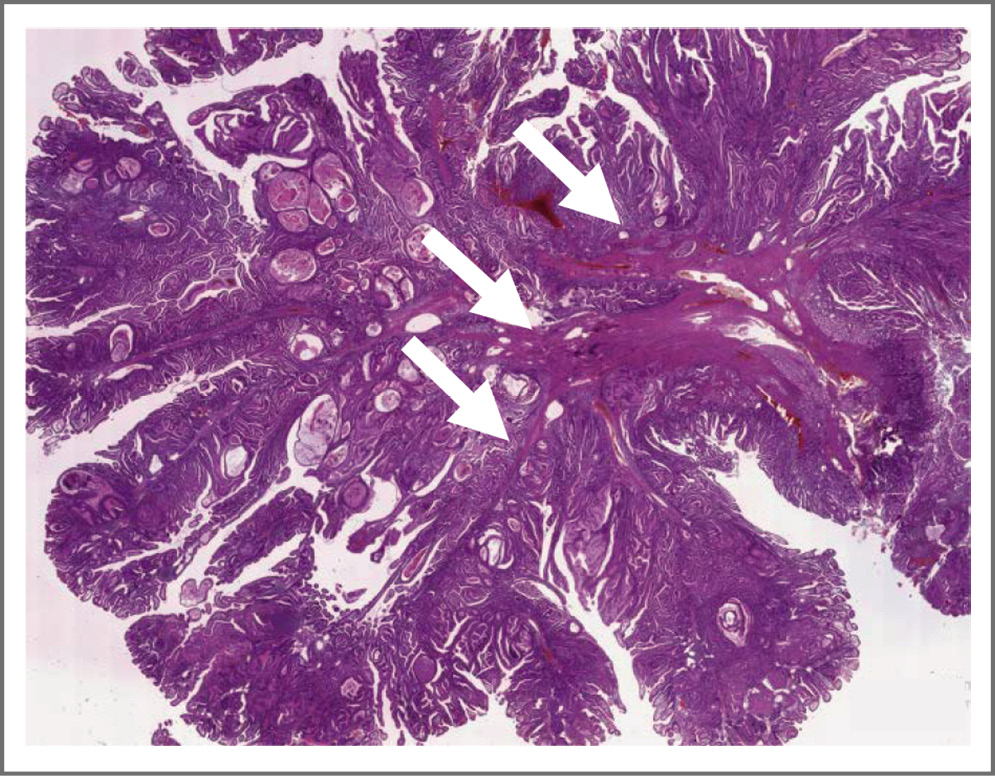

Все удаленные полипы имели строение, характерное для полипов Пейтца–Егерса (рис. 3). Следует отметить, что в других учреждениях согласно результатам гистологического исследования неоднократно выявлялись ворсинчатые аденомы с разной степенью дисплазии.

Рис 3. Типичное морфологическое строение гамартомного полипа тонкой кишки при СПЕ (окраска гематоксилин и эозин, увеличение ×5). Древовидно ветвящиеся пучки гладкомышечных волокон указаны стрелками. / Fig 3. Typical morphological structure of hamartomatous polyp of the small intestine in Peutz–Jeghers syndrome (hematoxylin and eosin, ×5). Tree-branching bundles of smooth muscle fibers are indicated by arrows.